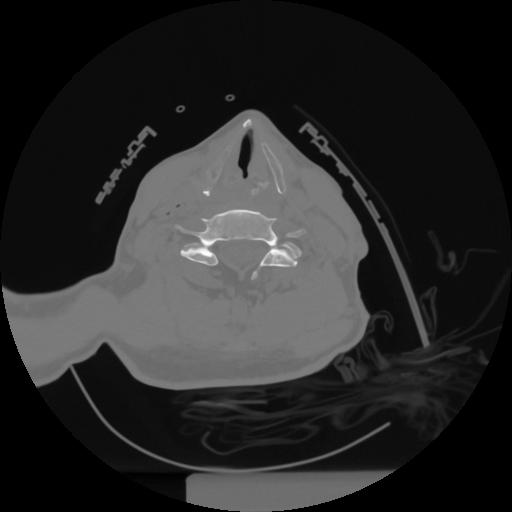

12 P.BLANDAS,,Vol,0.5,P.BLANDAS,,